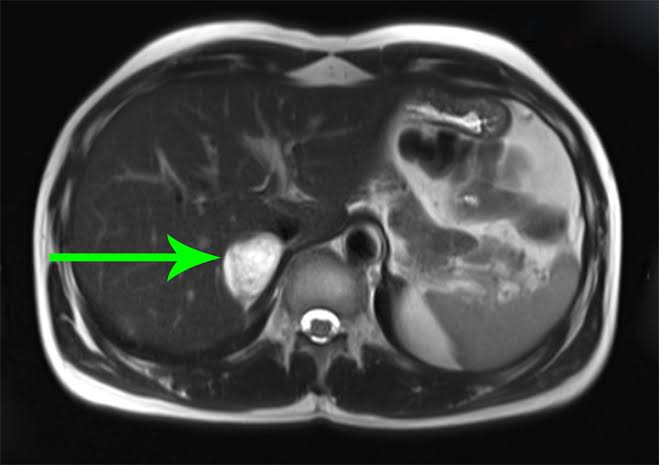

Não é raro que a adrenal seja local de desenvolvimento de tumores. Esses tumores geralmente são descoberto ao acaso, situação em que chamamos de incidentaloma adrenal.

1. Sintomas e sinais típicos (hipertensão, cefaleia, palpitação, sudorese etc) combinados com aumento dos níveis de metanefrinas ou catecolaminas: realizar tomografia com contraste ou ressonância magnética;

2. Incidentaloma adrenal ou de massa retroperitoneal: se o exame que detectou incidentalmente a massa adrenal é uma tomografia sem contraste e tem um atenuação dos feixes de RX da massa de 10 unidades Hounsfiel (UH) ou menos, descarta-se feocromocitoma e não é necessário fazer os testes bioquímicos. Essa medida é geralmente fornecida no laudo do exame. Se a massa tiver > 10UH, complementar investigação;

Existem achados radiológicos nos casos suspeitos na tomografia e ressonância e que ainda podem ser complementados com exames de cintilografia documentar com mais segurança a localização anatômica desses tumores. Esse tópico poderá ser detalhado em publicações futuras.